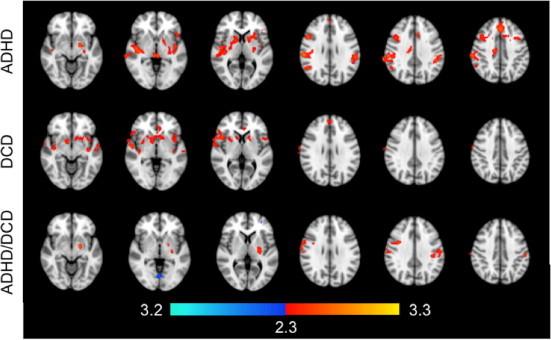

Developmental coordination disorder (DCD) and attention deficit/hyperactivity disorder (ADHD) are prevalent childhood disorders that frequently co-occur. Evidence from neuroimaging research suggests that children with these disorders exhibit disruptions in motor circuitry, which could account for the high rate of co-occurrence. The primary objective of this study was to investigate the functional connections of the motor network in children with DCD and/or ADHD compared to typically developing controls, with the aim of identifying common neurophysiological substrates. Resting-state fMRI was performed on seven children with DCD, 21 with ADHD, 18 with DCD + ADHD and 23 controls. Resting-state connectivity of the primary motor cortex was compared between each group and controls, using age as a co-factor. Relative to controls, children with DCD and/or ADHD exhibited similar reductions in functional connectivity between the primary motor cortex and the bilateral inferior frontal gyri, right supramarginal gyrus, angular gyri, insular cortices, amygdala, putamen, and pallidum. In addition, children with DCD and/or ADHD exhibited different age-related patterns of connectivity, compared to controls. These findings suggest that children with DCD and/or ADHD exhibit disruptions in motor circuitry, which may contribute to problems with motor functioning and attention. Our results support the existence of common neurophysiological substrates underlying both motor and attention problems.

发育性协调障碍(DCD)和注意缺陷多动障碍(ADHD)是常见的儿童期疾病,且经常同时出现。神经影像学研究的证据表明,患有这些疾病的儿童表现出运动神经回路的紊乱,这可能解释了它们的高共病率。本研究的主要目的是调查与发育正常的对照组相比,患有DCD和/或ADHD的儿童运动网络的功能连接,以确定共同的神经生理基础。对7名患有DCD的儿童、21名患有ADHD的儿童、18名患有DCD+ADHD的儿童和23名对照组儿童进行了静息态功能磁共振成像(fMRI)检查。以年龄作为协变量,比较了每组与对照组之间初级运动皮层的静息态连接性。相对于对照组,患有DCD和/或ADHD的儿童在初级运动皮层与双侧额下回、右侧缘上回、角回、岛叶皮质、杏仁核、壳核和苍白球之间的功能连接性有类似程度的降低。此外,与对照组相比,患有DCD和/或ADHD的儿童表现出与年龄相关的不同连接模式。这些发现表明,患有DCD和/或ADHD的儿童表现出运动神经回路的紊乱,这可能导致运动功能和注意力方面的问题。我们的结果支持运动和注意力问题存在共同的神经生理基础。